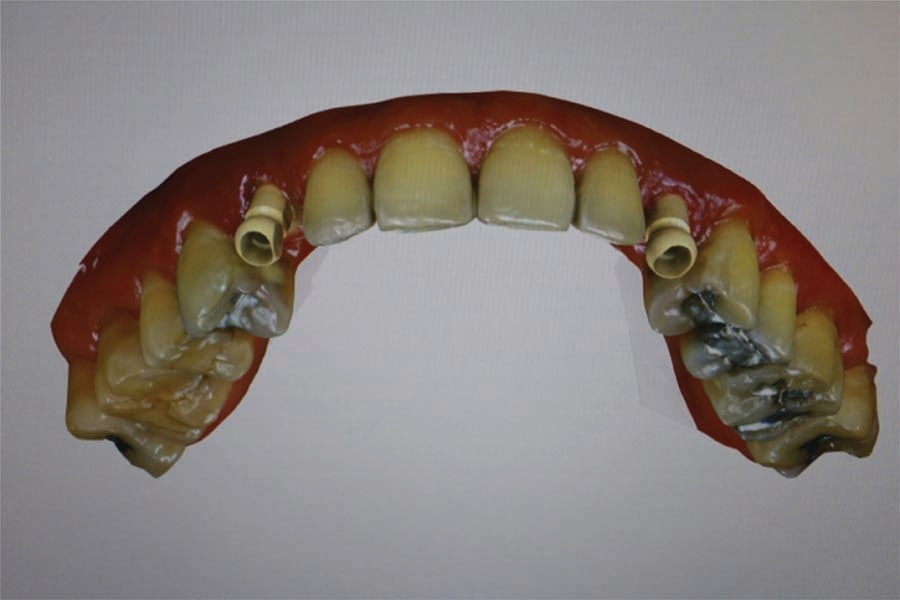

The patient returned and the healing abutments were removed. The gold-plated custom abutments from Atlantis were inserted, and the screw was hand tightened (Figure 18 and Figure 19). A radiograph was taken to verify the complete mating of the abutments with the implant’s connector. The screw was tightened to 25 ncm with a torque wrench. A piece of PTFE tape was placed into the screw access channel of the abutment and the provisional crowns were tried in. Fit and occlusion were verified. The provisional crowns were cemented to the abutment with Temp-Bond (Kerr Dental). Following setting of the cement the restoration margins were cleaned with an instrument to remove any residual cement. The occlusion was checked and the patient dismissed. The patient will wear the provisional crowns for a period of time to allow the gingival tissue to adapt to the crown’s contours before fabrication of the final crowns.

At 2.5 months post insertion of the provisional crowns the patient presented, and the gingival marginal position remained stable and had not changed since provisional crown placement. An absence of gingival inflammation was noted, and the tissue appeared healthy. The clinicians were confident that tissue maturation and emergence profile was complete. The patient was dismissed and the lab notified to fabricate the final crowns with similar contours to the provisional crowns they had fabricated.

The patient returned and the provisional crowns were removed and cement cleaned from the abutments. The final crowns (lab processed from Jason J. Kim Dental Aesthetics) were tried in and margins checked with an instrument. The occlusion was checked and verified light occlusion was present on occlusion and there were no contacts in excursive movements. The crowns were cemented to the abutments with FujiCEM. Following setting of the cement marginal cement was cleaned with an instrument and a radiograph taken to confirm crown fit to the abutments and no residual cement subgingivally (Figure 20). The patient was given a mirror to evaluate the esthetics of her new smile and indicated she was happy with results, commenting it looked natural (Figure 21 through Figure 24). She was placed on regular 6-month prophy recall.